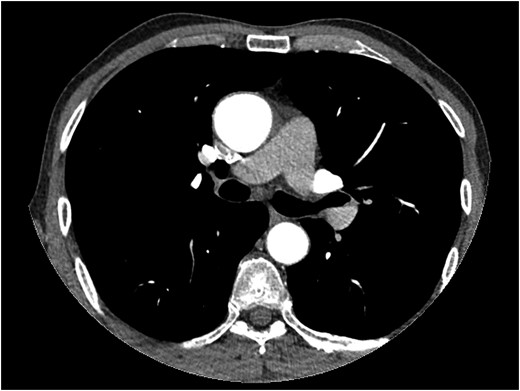

Meanwhile, TEE revealed myxomatous mitral and aortic valve, severe aortic valve insufficiency, moderate to severe mitral valve insufficiency, mild tricuspid valve insufficiency, ascending aorta and sinus valsalva dilation of 46 mm. A contrast computed tomography (CT) scan was performed and revealed ascending aorta dilatation of 48.5 mm without aortic dissection and sinus valsalva of 46 mm (Fig. 1). The descending aorta appeared to be normal, measuring 26.5 mm at its widest diameter.

Thorax CT angiography showing the dilatation of ascending aorta of a patient before surgery on admission to our center.